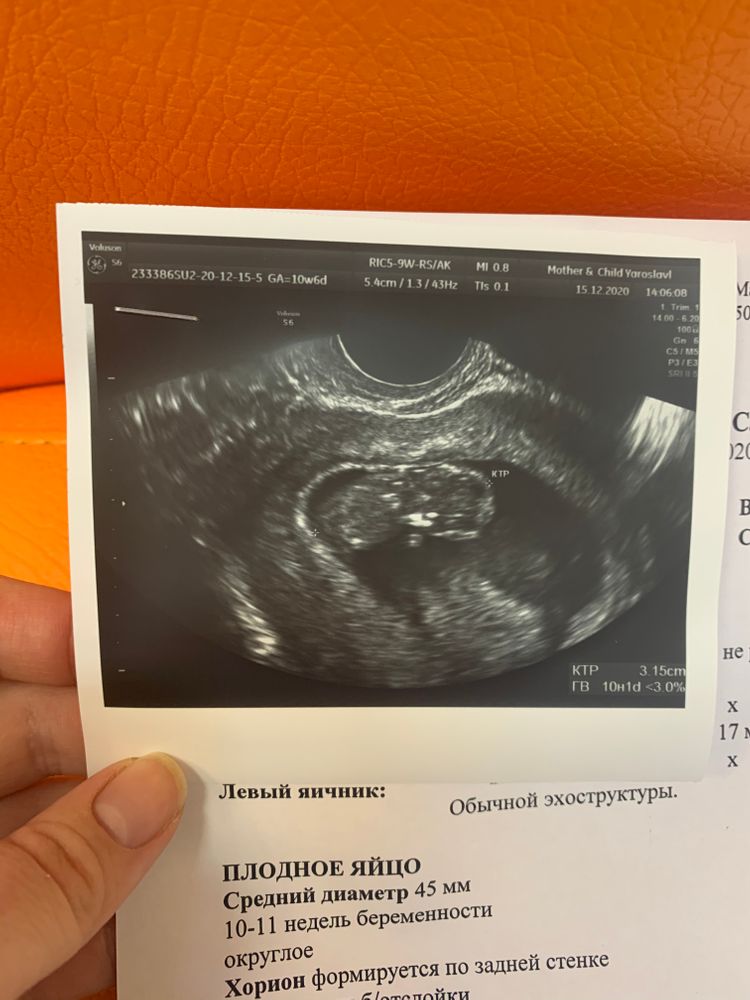

Узи 10 неделек

15.12.2020